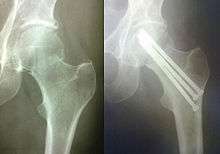

Osteosynthesis is the reduction and internal fixation of a bone fracture with implantable devices that are usually made of metal. It is a surgical procedure with an open or per cutaneous approach to the fractured bone. Osteosynthesis aims to bring the fractured bone ends together and immobilize the fracture site while healing takes place. In a fracture that is rigidly immobilized the fracture heals by the process of intramembranous ossification.